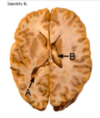

Label the arteries that supply A-C [3]

A = anterior cerebral artery (upper

and medial parts of the cortex)

(orange)

B = middle cerebral artery (lateral

areas of the frontal, parietal, and

temporal lobes) (white)

C = posterior cerebral artery (occipital

lobe and inferior parts of the

temporal lobe) (blue)